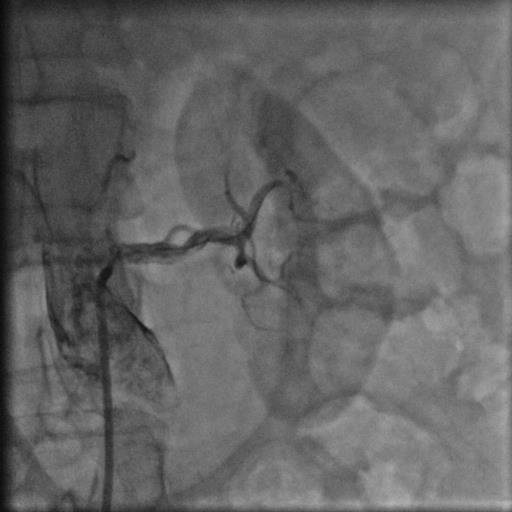

44 yaşında şeker hastalığı olan hastamız dirençli yüksek tansiyon şikayetiyle bize başvurdu. Herhangi bir sebep bulunamayan hastamız 2 yıldan beri cesitli ilaçlar kullanmasına rağmen tansiyonunun düşürülemediğini söylüyordu. Yaptiğımız detaylı muayene ve tetkikler sonucu böbrek damarının tıkalı olduğunu tesbit ettik ve yaptıgımız stent işlemi sonrasında hastamız normal tansiyon değerleriyle taburcu edildi..